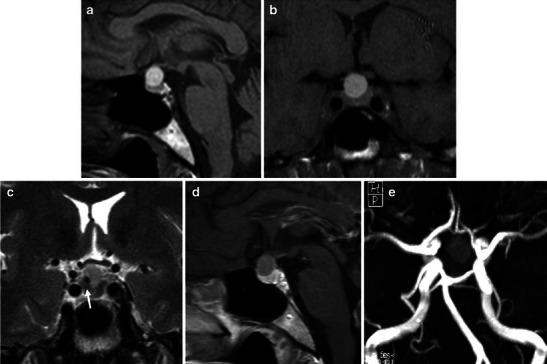

垂体卒中:临床及影像学特征的最新进展

Pituitary apoplexy: an update on clinical and imaging features.

Pituitary apoplexy (PA) is a rare and potentially fatal clinical condition presenting acute headache, vomiting, visual impairment, ophthalmoplegia, altered mental state and possible panhypopituitarism. It mostly occurs in patients with haemorrhagic infarction of the pituitary gland due to a pre-existing macroadenoma. Although there are pathological and physiological conditions that may share similar imaging characteristics, both clinical and imaging features can guide the radiologist towards the correct diagnosis, especially using magnetic resonance imaging (MRI). In this review, we will describe the main clinical and epidemiological features of PA, illustrating CT and MRI findings and discussing the role of imaging in the differential diagnosis, prognosis and follow-up. Teaching points • Headache, ophtalmoplegia and visual impairment are frequent symptoms of pituitary apoplexy. • CT is often the first imaging tool in PA, showing areas of hyperdensity within the sellar region. • MRI could confirm haemorrhage within the pituitary gland and compression on the optic chiasm. • Frequent simulating conditions are aneurysms, Rathke cleft cysts, craniopharingioma and mucocele. • The role of imaging is still debated and needs more studies.

垂体卒中(PA)是一种罕见且可能致命的临床病症,表现为急性头痛、呕吐、视力障碍、眼肌麻痹、精神状态改变以及可能出现的全垂体功能减退。它大多发生于因先前存在的大腺瘤导致垂体出血性梗死的患者。尽管存在一些可能具有相似影像学特征的病理和生理状况,但临床和影像学特征均可引导放射科医生做出正确诊断,尤其是使用磁共振成像(MRI)时。在本综述中,我们将描述垂体卒中的主要临床和流行病学特征,阐述CT和MRI表现,并讨论影像学在鉴别诊断、预后及随访中的作用。教学要点 • 头痛、眼肌麻痹和视力障碍是垂体卒中的常见症状。 • CT通常是垂体卒中的首选影像学检查工具,显示鞍区内的高密度区域。 • MRI可确认垂体出血及对视交叉的压迫。 • 常见的相似病症有动脉瘤、拉克氏囊肿、颅咽管瘤和黏液囊肿。 • 影像学的作用仍存在争议,需要更多研究。